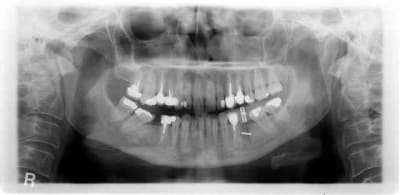

pour changer de sujet

un échec d'endo.

première consult en 3/2009 atteinte de 35

dépose de la ccm repirse d'endo repose de la ccm tenon raccourci

mais évolution+++ de la lésion qui m'a conduit à l'avulsion de la dent en septembre curetage soigneux et mise en place de : rien

en janvier pano de controle avec petit repère (tige maillefer recoupée à 10mm) dans du silicone

janvier pose d'un natéa en 4.1*10

pas de photo désolé

comme quoi, ne rien mettre donne aussi de bons resultats...

pour humator : non en fait si tu regardes endo paro en mesial

pour pxav : surface de contact os implant en 4.1*10 superieur a 12*3.3 et en plus le mentonnier fait sa boucle juste la c'est pour ça que pas plus long